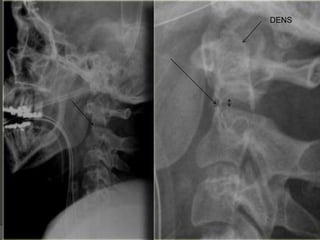

C1-C2

Predental space

(distance between posterior

aspect of anterior arch of C1

and anterior aspect of

odontoid process )



should be< 3mm In adult

and less <5mm in children

Or less

 ring sign of C2

Odontoid View

An adequate film should include the

entire odontoid and the lateral

borders of C1-C2.

Occipital condyles should line up with

the lateral masses and superior

articular facet of C1.

The distance from the dens to the

lateral masses of C1 should be equal

bilaterally.

The tips of lateral mass of C1 should

line up with the lateral margins of the

superior articular facet of C2.

The odontoid should have

uninterrupted cortical margins

blending with the body of C2.

DENS

The image through the lateral part of C2 nicely shows, that the fracture runs

through the body of C2, i.e. a type III odontoid fracture.

The posterior dura is in a normal position, but the anterior dura is displaced

(arrow).

Showing Central location of spinal cord injury